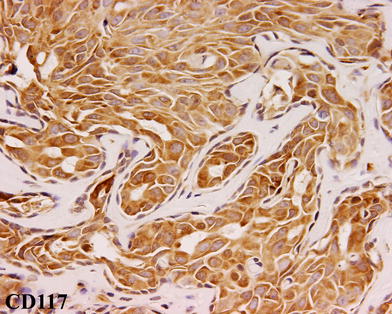

Fig. 11

Ceruminous adenocarcinoma, NOS. Note the strong reaction with CD117 in the tumor cells

All lesions tested reacted strongly and diffusely with a keratin cocktail and with epithelial membrane antigen (Table 6). Where the surface epithelium was present, it was strongly and diffusely immunoreactive for the epithelial markers analyzed, and served as an internal quality control. The dual cell population was accentuated by the immunohistochemical studies. The luminal cells were strongly immunoreactive with CK7 and with CD117 (Fig. 11). The basal-myoepithelial cells were strongly and diffusely reactive in both the nucleus and cytoplasm with S-100 protein (63%), in the cytoplasm with CK5/6 (50%) and in the nucleus only with p63 (38%; Fig. 12). Thirty-seven percent of cases tested demonstrated Ki-67 immunoreactivity ranging from 2+ to 3+, affecting greater than 5% of the nuclei in the specimen, while the others showed <1% reactivity. p53 was identified in 57% of cases; although immunoreactivity ranged from 1+ to 3+, less than 10% of the nuclei in the specimen were affected in 3 cases, while 1 case demonstrated reactivity in about 30% of nuclei. CK20 was negative in all cases tested.